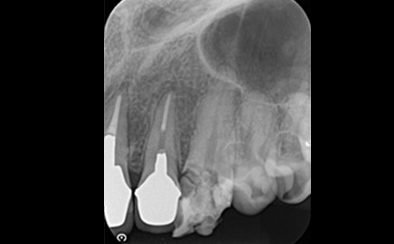

治療前

治療後

写真の白丸部分に膿が溜まっていて痛みと腫れがあり、半年も続いているそうです。これを治療した歯科医師はこれで治らなかったら抜歯してインプラント治療という選択をしました。

歯の状況や、顎骨の状況、また、患者さんご自身からもできるだけ自分の歯を残したいというご希望だったので、精密根管治療を天然歯の保存を目的として計画しました。

まず、根管内のガッタパーチャ(根管充填材)を除去、さらにマイクロスコープによる拡大視野とラバーダム防湿法により丁寧に汚れを除去しました。根管内の感染源がなくなったことを確認したうえで、通常のガッタパーチャとシーラーでは緊密な根管充填ができないと診断し、患者さんに説明したうえでMTA (ProRoot MTA)を選択しました。

3回の治療を行った後、痛みと腫れ、また上の画像にあった丸印の膿の袋もなくなっています。ということは、インプラントせずにこの上にクラウンを被せて治療を終了することができます。

| 費用 | コア除去:22,000円 根管治療:132,000円 MTA根管充填:33,000円 合計:209,000円 |